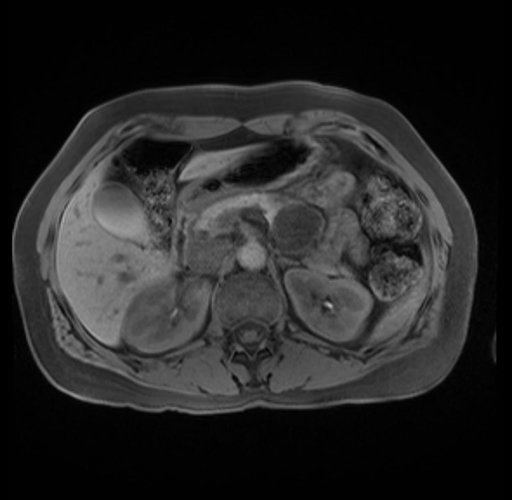

Imaging Analysis

Look through the patient's CT scan to identify any areas of concern for the necessary procedure.

Based on your CT findings, which issue(s) are present and would give reason for "planned slowing down moment(s)" in this case?

Considering a standard distal pancreatectomy procedure, what step(s) of the operation would you do differently in this case?